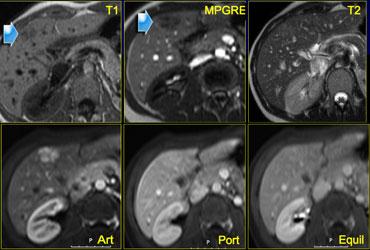

Cùng ca bệnh trên MR động học.

Lưu ý cách MR thể hiện rõ kiểu ngấm thuốc ngoại vi dạng nốt, lan dần vào trung tâm (mũi tên cong màu xanh) mà CT không thể hiện được.